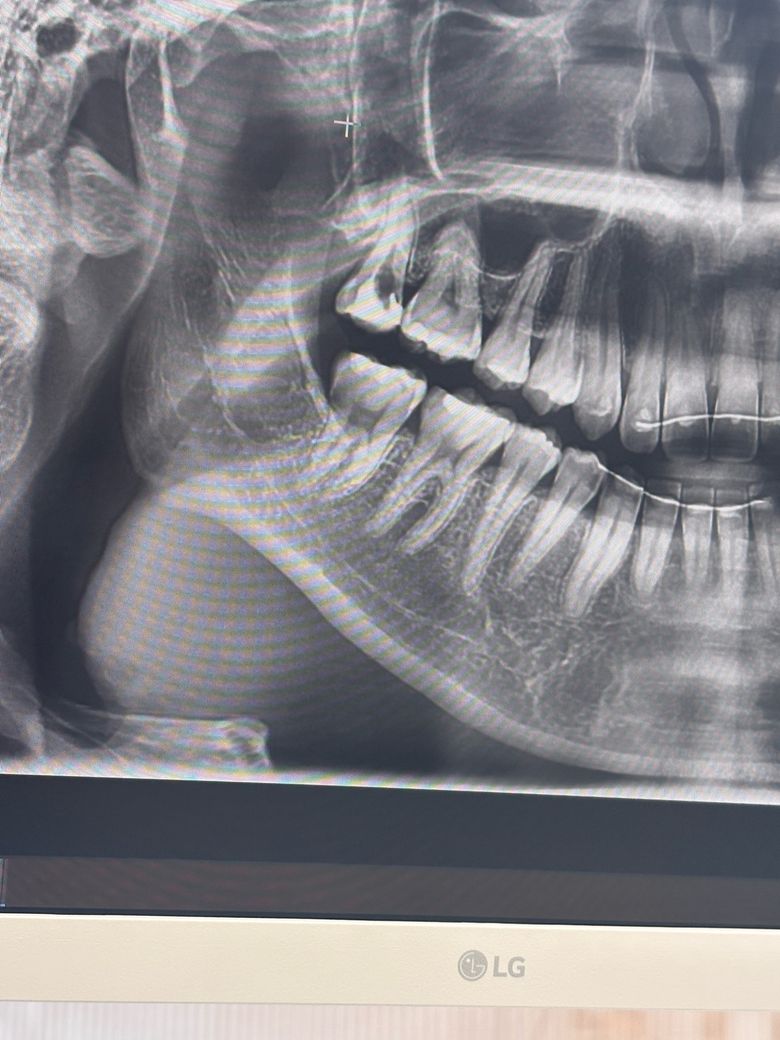

엑스레이 왼쪽 끝에 어금니 신경치료만 4회 방문하였는데 설명하나 없이 진행중이라 잘되어가는 것인지 궁금합니다. 매번 설명없이 진행하여 다른 치과에서 상담빋은 상황인데 옮기는게 나을까요?

오른쪽 위 맨뒤 어금니 말씀하시는 것 같습니다

신경관 찾고, 확대가 되어있는 것 같습니다

엑스레이로 알 슈 있는 건 이정도이고 신경치료가 잘되었는지 실질적으로 평가는 직접보지않는한 어렵습니다

증상이 바로 사라지지 않고 점차 사라지는 경우이거나 치아에 금이가서 아픈경우입니다 치아에 금이 간 경우 일단 신경치료 마치고 자발통이 없다면 크라운으로 씌워주어야 증상이 사라지기도 합니다